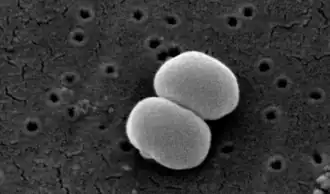

| SEM micrograph of S. aureus colonies; the grape-like clustering is common to Staphylococcus species. | |

The generic name Staphylococcus is derived from the Greek word "staphyle", meaning bunch of grapes, and "kokkos", meaning granule. [39]

The bacteria, when seen under a microscope, appear like a branch of grapes[40]